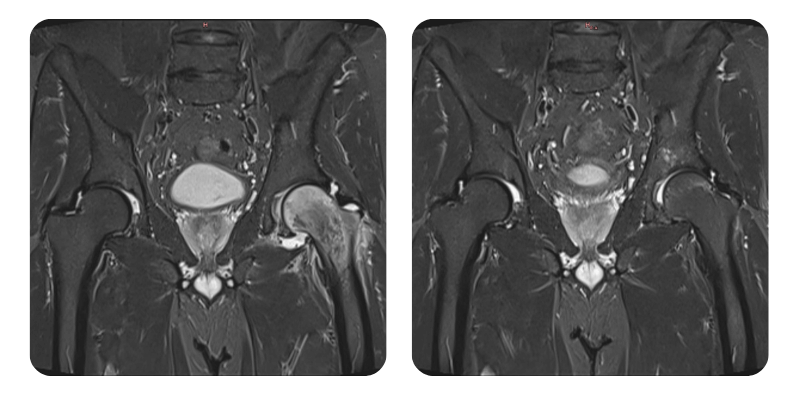

Előtte

Utána

J.A.V., 43 éves – Bal combfej ödéma

Diagnózis: Bal combfej ödéma.

A klinikai eredményekkel összhangban az ödéma több mint 90%-kal csökkent, a páciens gyógyultnak tekinthető.